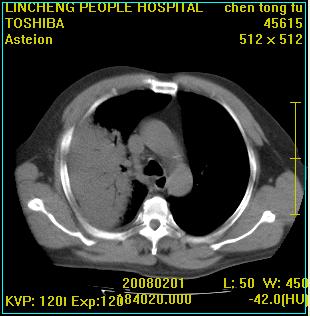

患者,男性,62岁。主因头晕,发热,咳嗽6天,高热达39度,esr19mm/h,wbc 3.9×10 9/l

大叶性肺炎并胸膜炎

右肺大叶性肺炎,胸腔积液。建议痰检。

实变区见空气支气管征,支气管通畅,考虑为大叶性肺炎,右侧少量胸水

1)考虑为:右肺感染性病变。建议:抗炎治疗复查。2)右侧少量胸腔积液。

考虑为右肺大叶性肺炎,胸腔积液,建议必要时纤维支气管镜检查,以排除肿瘤性病变。

右肺炎症并右侧胸腔少量积液。

考虑为右肺大叶性肺炎伴少量胸腔积液,建议复查,如病变不吸收或吸收不明显,建议纤维支气管镜检查,除外细支气管肺泡癌的可能。

右侧大叶性肺炎,右侧少量胸腔积液.